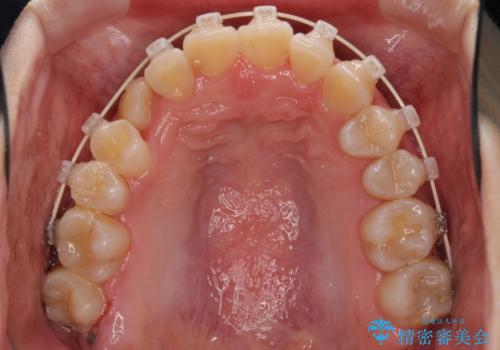

- 矯正装置

- 審美装置

- 前歯のでこぼこと乳歯が残るほどの八重歯を気にして来院された患者様です。

非抜歯にてワイヤー矯正にて治療することとしました。(ただし、親知らずと乳歯は抜歯)

犬歯は歯根が太く長いため、移動には時間を要します。しかし、犬歯は機能面から考えて残すことを選択したいため、長期間をかけて治療を行うこととしました。

治療の度に歯列が改善していったため、長期間の治療も楽しく過ごしていいただき、満足のいく仕上がりとなりました。